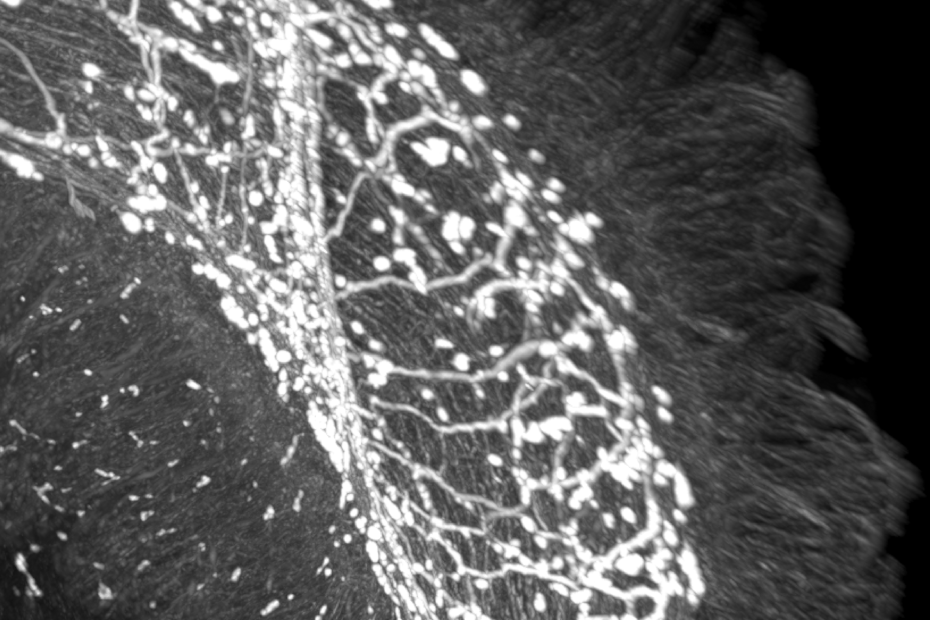

Forschende am Champalimaud Centre for the Unknown in Lissabon haben entdeckt, wie das Nervensystem im Darm entscheidet, ob das Immunsystem angreift oder repariert. Die Studie, veröffentlicht in „Nature Immunology“, beschreibt erstmals einen direkten Dreier-Dialog zwischen Darmnerven, den deckenden Epithelzellen und dem Immunsystem – und identifiziert dabei den Neurotransmitter VIP (vasoaktives intestinales Peptid) als zentrale Schaltstelle.

VIP wird von bestimmten Darmneuronen freigesetzt, wenn wir essen. Epithelzellen, die die Darmwand auskleiden, tragen den Rezeptor VIPR1 und empfangen das Signal. Je nachdem, ob VIPR1 aktiviert oder blockiert wird, produziert die Epithelzelle unterschiedliche Botenstoffe (Zytokine), die das Immunsystem in zwei gegensätzliche Programme lenken:

Tierversuche zeigten dramatische Effekte: Mäuse ohne VIPR1 in den Epithelzellen waren deutlich anfälliger für bakterielle Infektionen wie Salmonella, aber besser gegen Parasiten geschützt. Das Nervensystem im Darm fungiert damit wie eine Weiche, die je nach Situation den passenden Immunweg wählt.